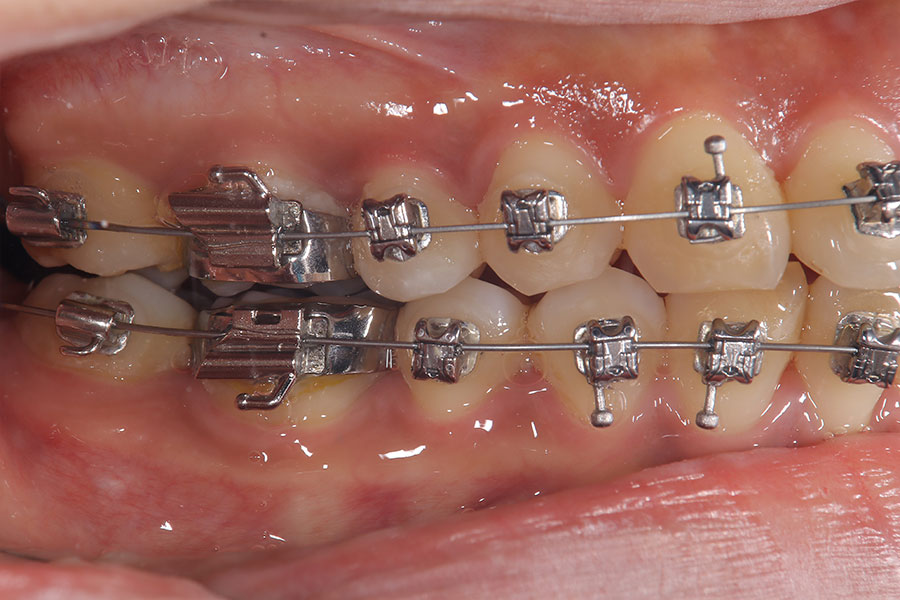

Before -側面-

After -側面-

| 施術内容 | ワイヤー矯正から、目立ちにくくメタルフリーなインビザラインへ変更しました。 金属アレルギーの不安が軽くなり、取り外しできることで清掃性も向上。見た目も自然で、治療中のストレスが少ない矯正方法です。 |

|---|---|

| 治療期間 | 2年間 |

| 費用 | インビザラインフル 767,800円 リテーナー 30,000円 |

| リスク・副作用 | 治療にともない、歯の破折や歯質の削合、場合によっては抜歯が必要となることがあります。また、金属や補綴物を除去する際に、完全に除去できない場合もあります。 |